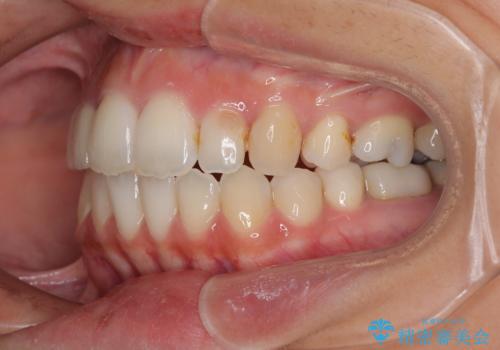

開咬と前突を改善 ワイヤー装置での抜歯矯正

- 口元の突出感と開咬を気にして来院された患者様です。

結果として下顎の小臼歯は抜歯せず、右上の抜歯スペースはむし歯処置を兼ねてオールセラミックブリッジにて補綴治療を行うこととしました。

動かない歯での停滞や、出産と子育てなどにより治療期間は長期化しましたが、整った歯列にて仕上げることができました。